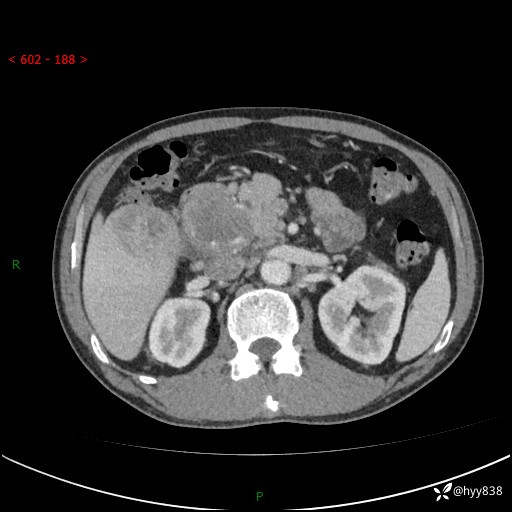

上腹部CT平扫+增强(两期)